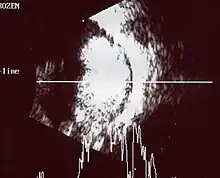

Traditional ultrasound B scan can detect calcifications in the tumour while high-frequency ultrasound B scan is able to provide higher resolution than the traditional ultrasound and determine the proximity of the tumour with front portion of the eye. MRI scan can detect high-risk features such as optic nerve invasion; choroidal invasion, scleral invasion, and intracranial invasion. CT scan is generally avoided because radiation can stimulate the formation of more eye tumours in those with RB1 genetic mutation.[24]

An ocular ultrasound of a large retinoblastoma tumor within the eye of a 3-year-old boy -

If the eye examination is abnormal, further testing may include imaging studies, such as computerized tomography (CT), magnetic resonance imaging (MRI), and ultrasound.[33] CT and MRI can help define the structure abnormalities and reveal any calcium depositions. Ultrasound can help define the height and thickness of the tumor. Bone marrow examination or lumbar puncture may also be done to determine any metastases to bones or the brain.